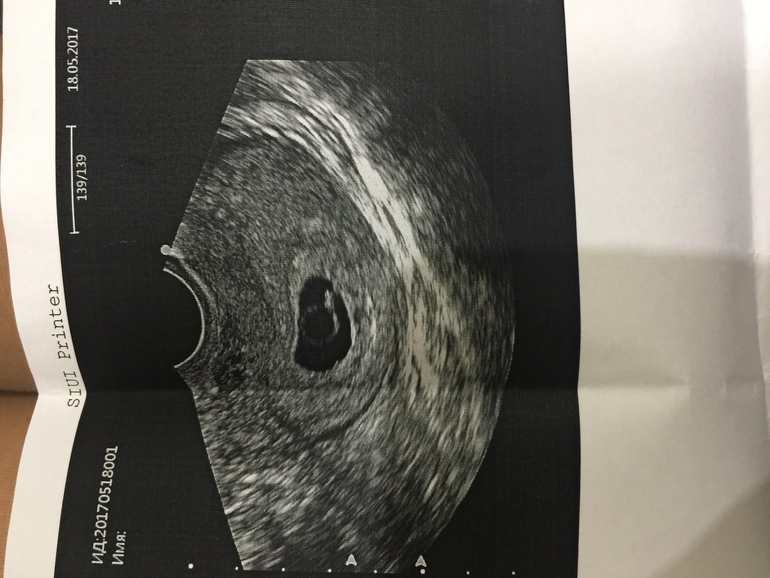

Пишу, чтобы тут выговориться, переживаю очень! Вчера была на УЗИ, последние мес 27.03, по календарю срок 7 недель и три дня, а узистка ( попалась конечно , не пойду больше к ней, ни капли такта) сказала, что срок 5 недель 4 дня! Я в панике! Эмбрион определяется , сердцебиение есть, но как она сказала не четкое. Я говорю он живой? Да говорит, но есть риск замершей! Как, если он живот, сердце бьется? Я чуть там не разрыдалась. Ушла из кабинета, тут же поехала в другую клинику, там врач меня немного успокоила, что такое может быть, поздняя овуляция и т д, сердцебиение подтвердила, рекомендовала контроль через 10 дней. Короче, незнаю что думать, и как 10 дней пережить. Может у кого было так , на первом УЗИ? Что срок расходился на две недели? Фото УЗИ прилагаю